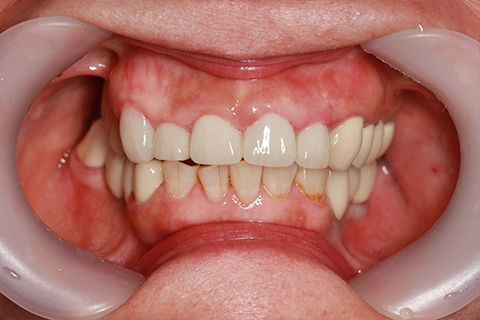

症例4

治療前

治療後

- 年齢・性別

- 60歳

- 治療期間

- 6ヶ月

- 抜歯

- 残根抜歯のみ

- 治療費

- 184.8万円

- 備考

- 右上5.6 右下5 左下4.5.6欠損

- 治療内容

- 6本のインプラントを右左側に2回に分けて埋入

- 施術の副作用(リスク)

- オペによる知覚障害。インプラントによる歯肉炎。インプラント脱落。